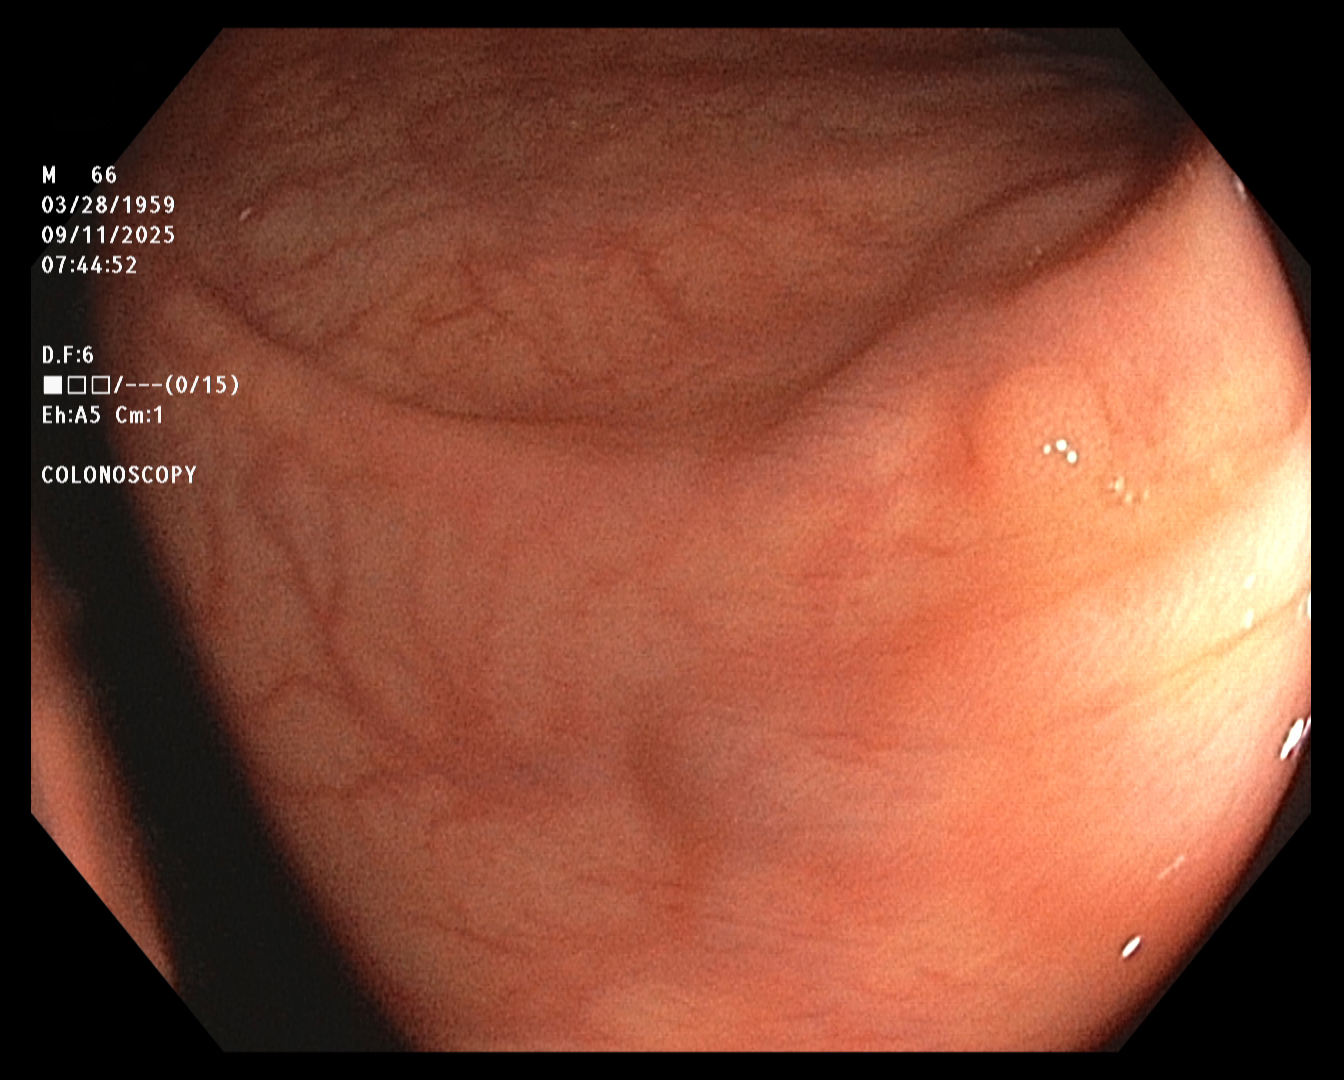

The endoscopist in this study generated a series of images showing the cecum and several sites

of concern (e.g., polyps). The cecum is the beginning of the colon, so reaching it ensures that

the entire colon will be examined. The endoscope was slowly withdrawn, while the endoscopist

assayed mucosal detail and identified and removed several polyps for later examination. The

first and last images were taken about twenty minutes apart.

Cecum